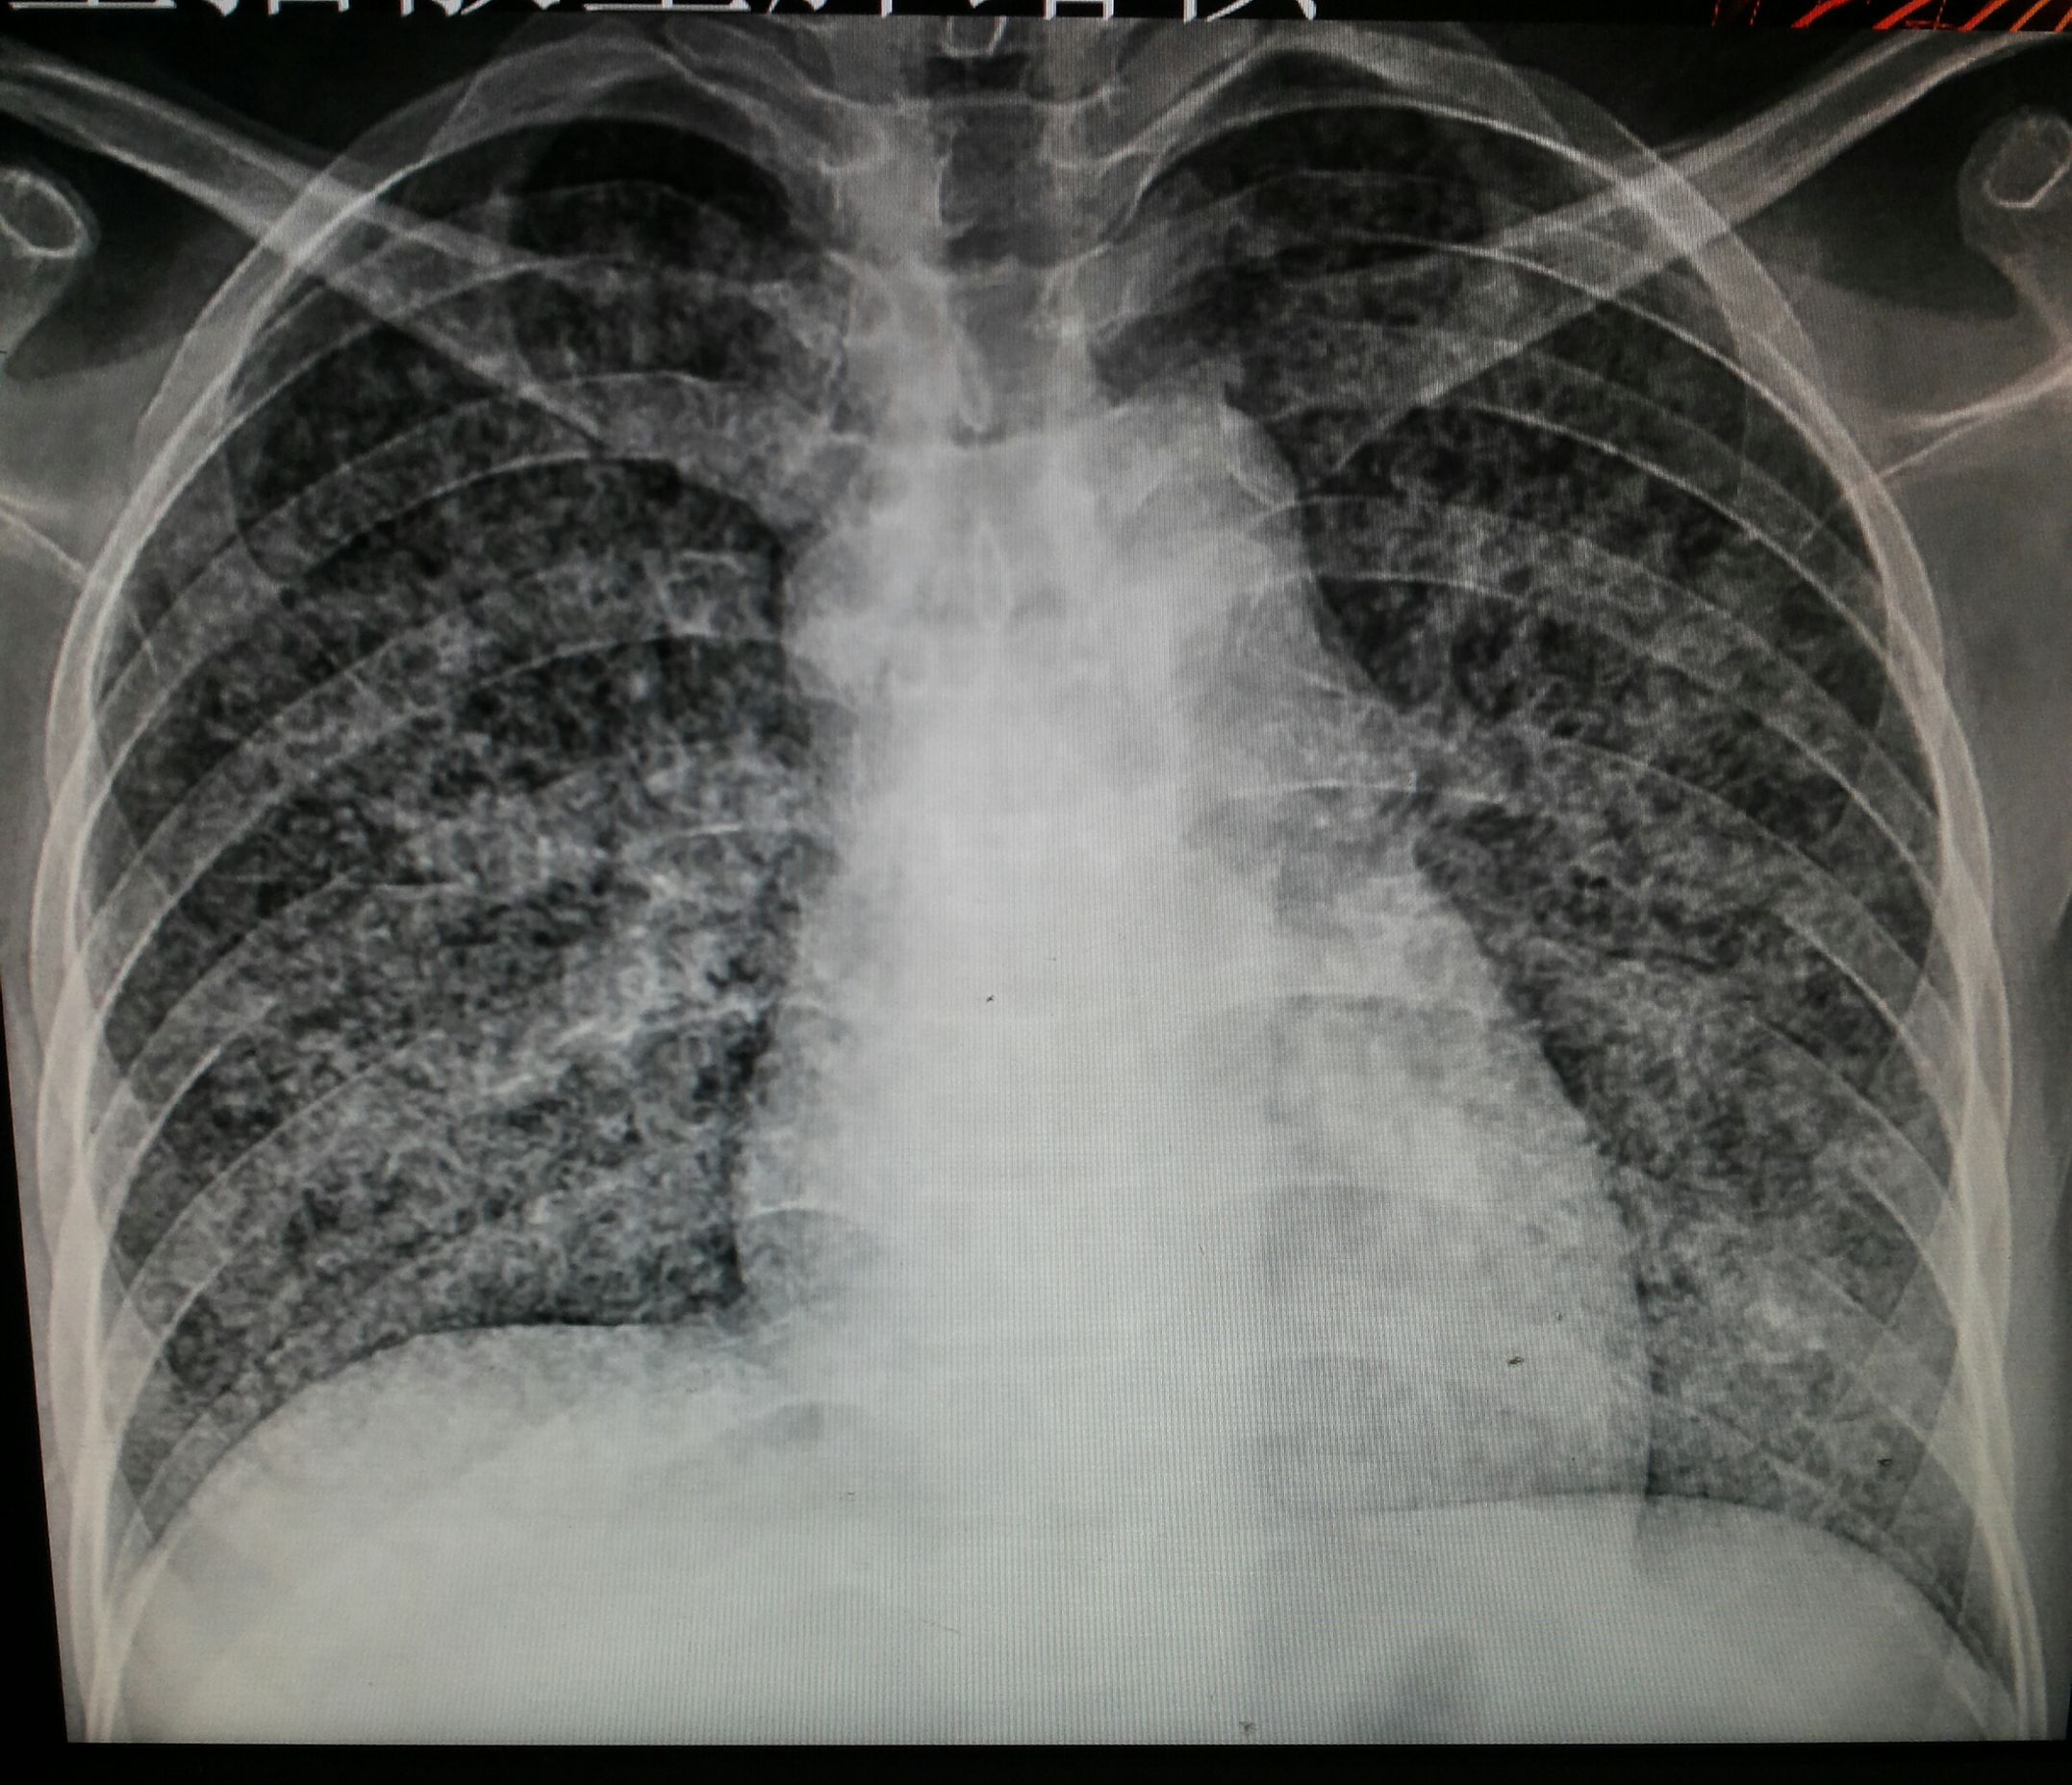

图片来源于网络

根据美国放射协会和妇产科协会的数据。胎儿受到的照射剂量高于5000mrad才会引起胎儿的损伤。但一次胸部拍片胎儿受到的照射剂量是0.02-0.07mrad。腹部平片胎儿受到的照射剂量是100mrad。肾盂静脉造影胎儿受到的照射剂量大于1000mrad。钡灌肠造影时,因为需要多次连续成像胎儿受到的照射剂量约2000-4000mrad。临床上已经较少用钡灌肠造影而是更长做胃肠镜。

CT检查放射剂量略大。但也和检查部位有关。如果是盆腔CT,胎儿受到了照射剂量是可以达到1500mrad。而其它部位肺部、头部因为远离盆腔。胎儿受到的照射剂量远远低于这个水平。近年来CT技术不断改进,医生可以使用低剂量CT。低剂量CT检查盆腔,胎儿接受的放射线剂量只有250mrad。你看这么多的检查项目都没有达到胎儿损伤的剂量。所以单次接受放射线检查剂量都非常的低,尤其是远离盆腔的检查不足以造成胎儿的损伤。